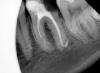

Мисс Опубликовано 27 ноября, 2012 Поделиться Опубликовано 27 ноября, 2012 (изменено) Подскажите как запломбированы каналы и нужно ли их перепломбировать.И как лучше восстановить этот зуб. Изменено 27 ноября, 2012 пользователем Мисс Ссылка на комментарий

shishok Опубликовано 27 ноября, 2012 Поделиться Опубликовано 27 ноября, 2012 При хорошем раскладе передние перелечивать обязательно(задние(й)-ревизия и, возможно, перепломбировка).Восстанавливать-вкладка+коронка.А с восьмёркой у Вас что?Снимка нет? Ссылка на комментарий

ger_berra Опубликовано 27 ноября, 2012 Поделиться Опубликовано 27 ноября, 2012 Все каналы надо перелечивать.Изолированная ревизия-это баловство. 1 Ссылка на комментарий